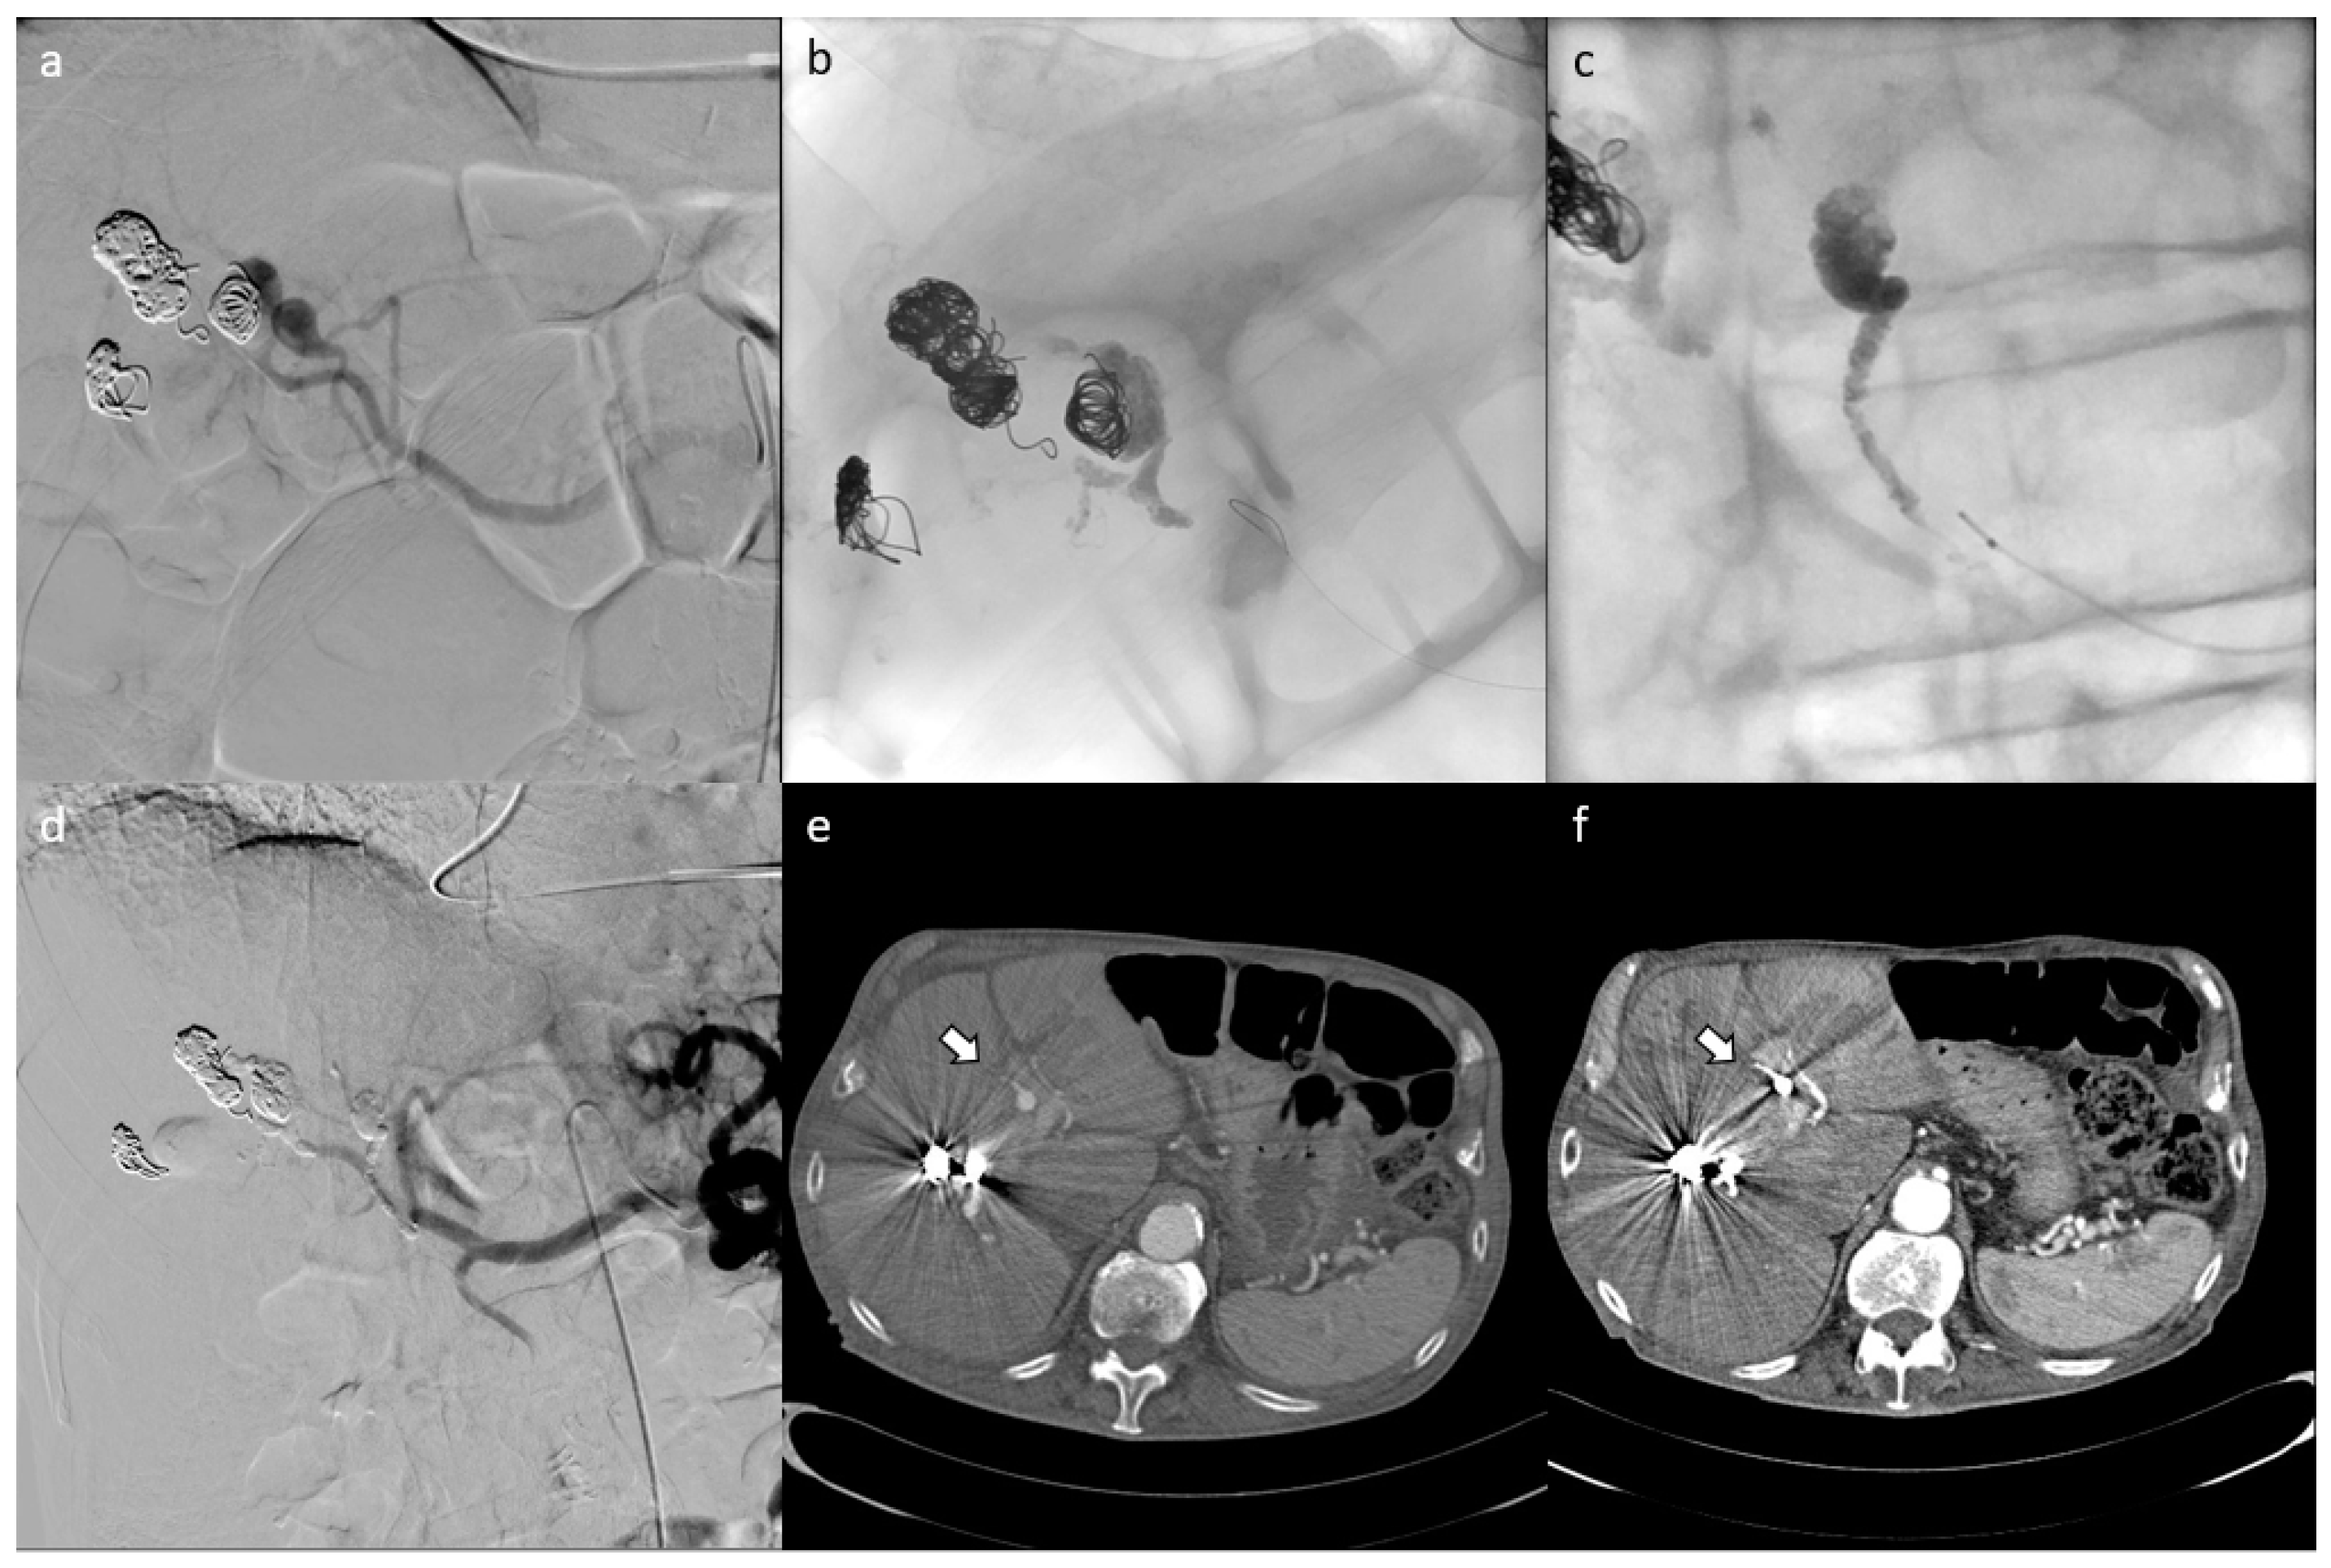

3. Results